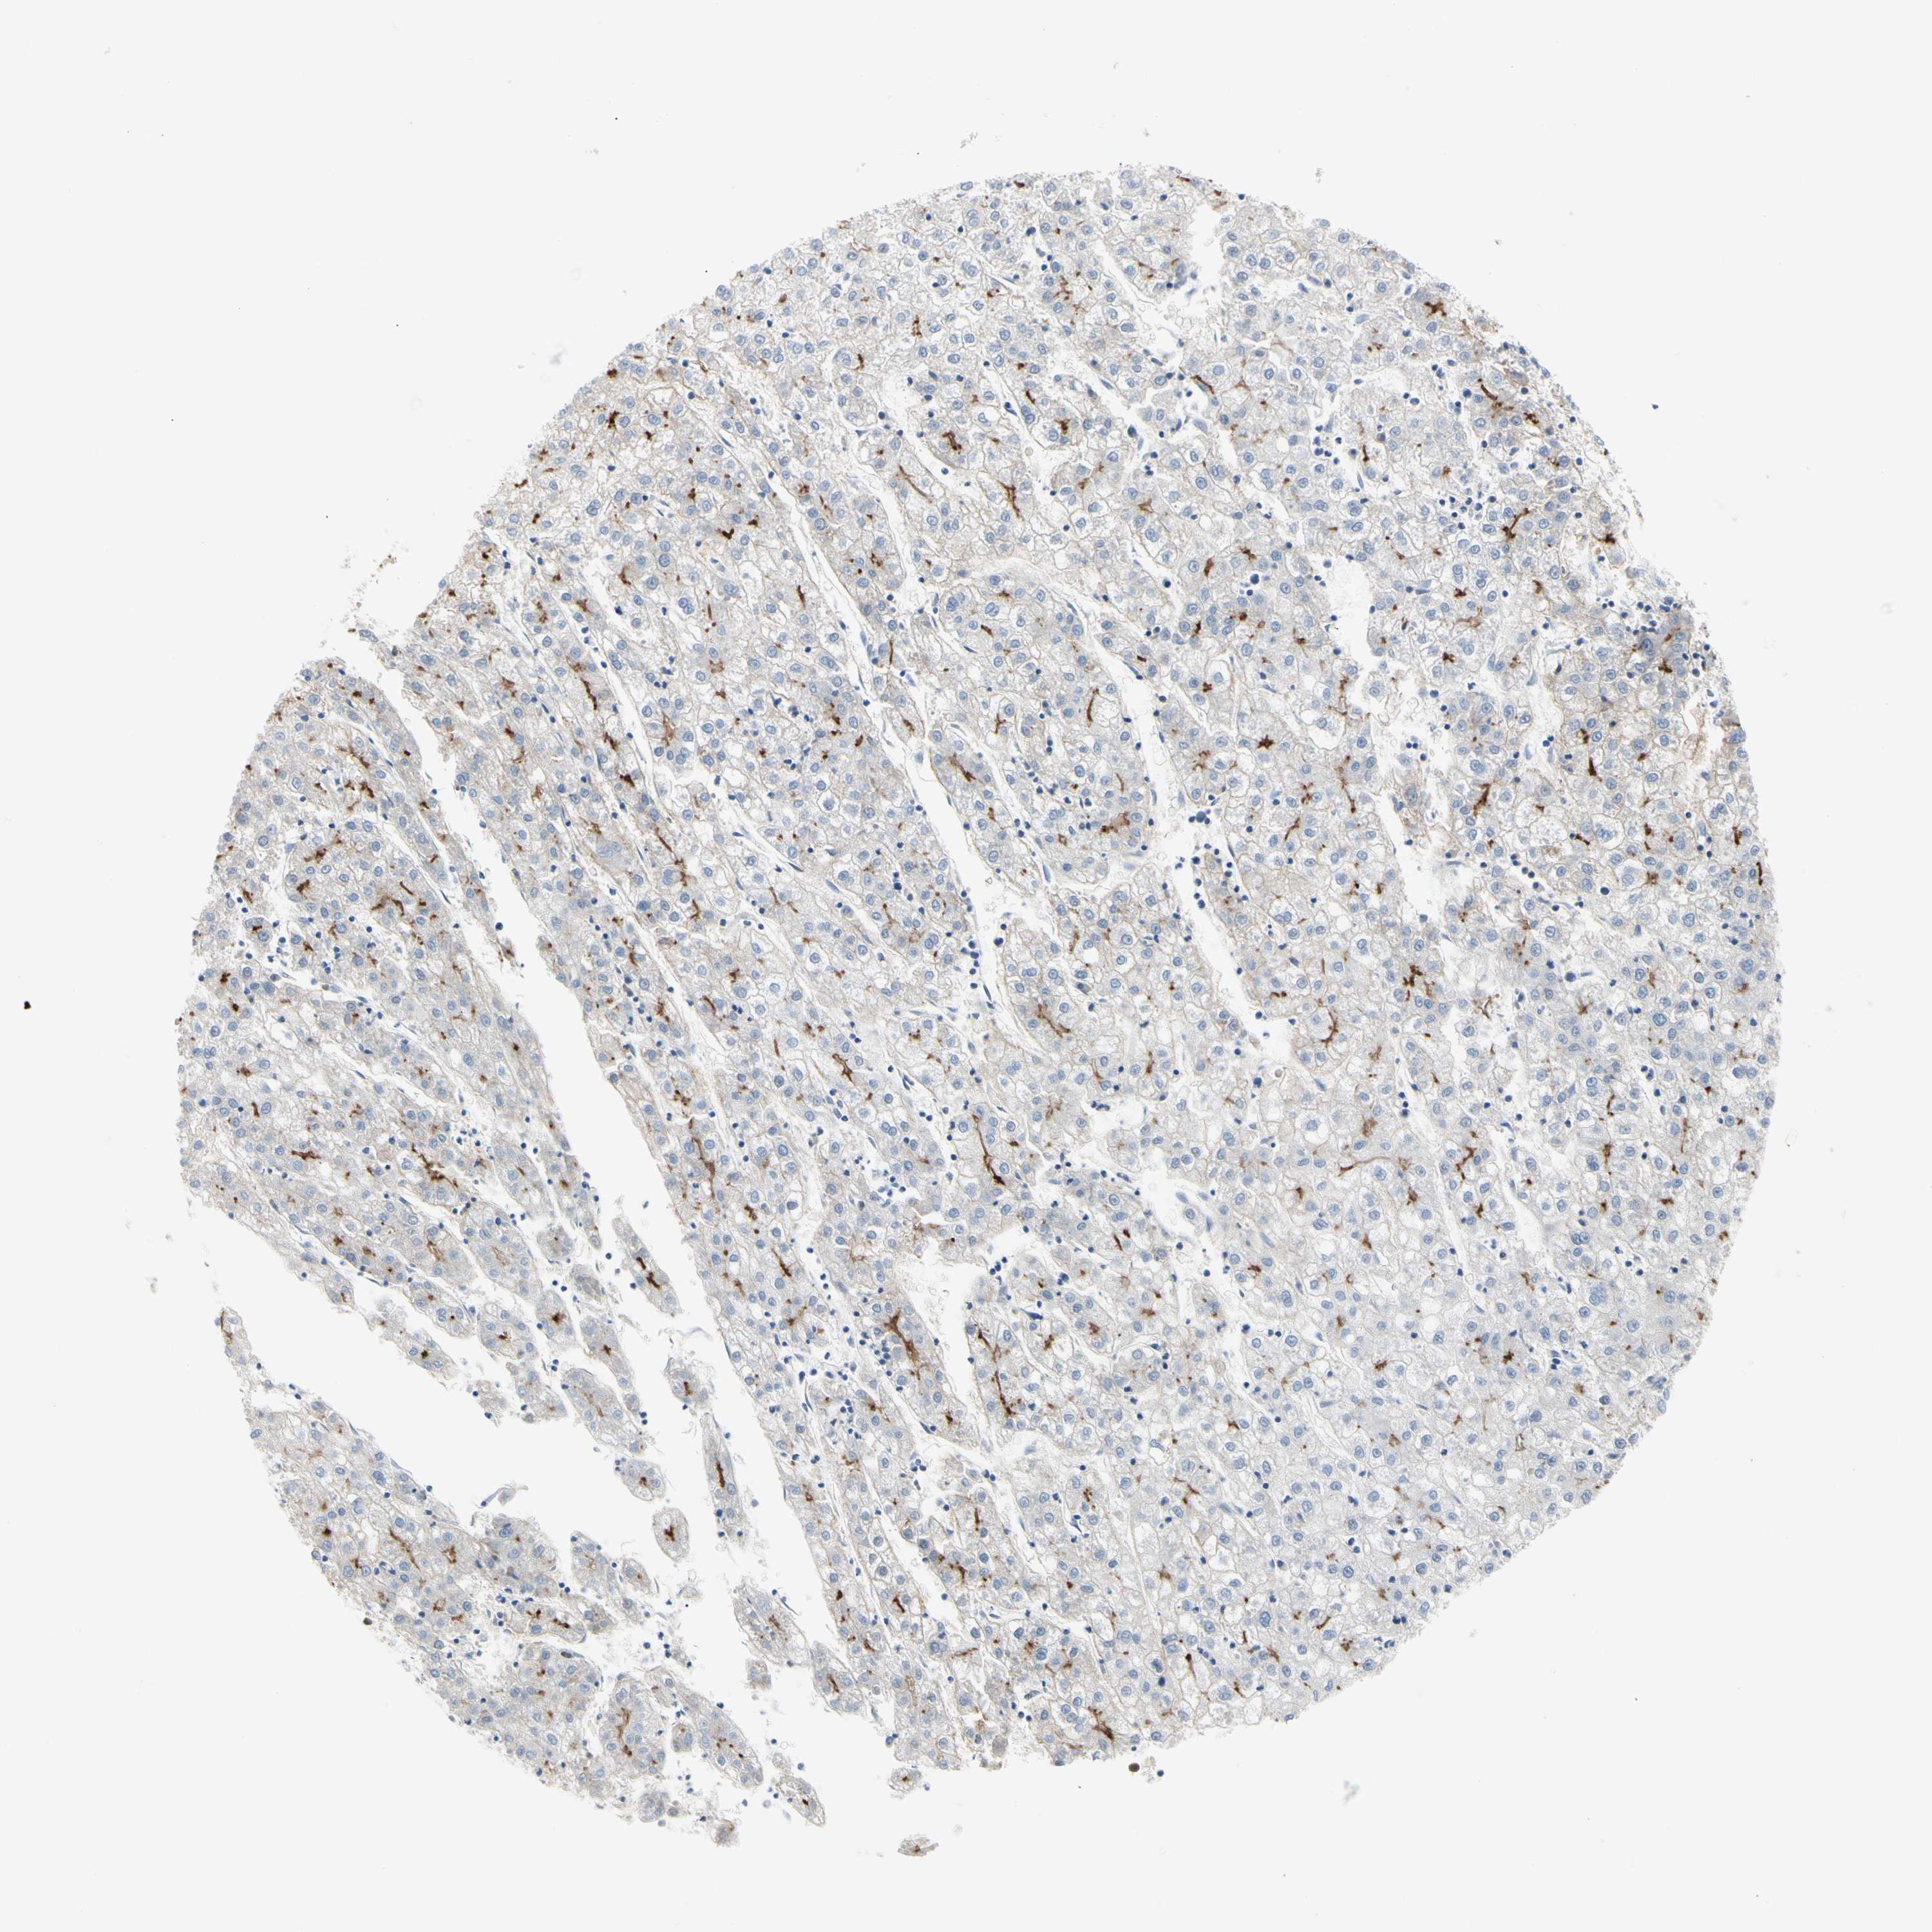

LIVER CANCER - Protein expressioni

A mouse-over function shows sample information and annotation data. Click on an image to view it in a full screen mode. Samples can be filtered based on level of antibody staining by selecting one or several of the following categories: high, medium, low and not detected. The assay and annotation is described here.

Note that samples used for immunohistochemistry by the Human Protein Atlas do not correspond to samples in the TCGA dataset.

Antibody stainingi

Antibody staining in the annotated cell types in the current human tissue is reported as not detected, low, medium, or high, based on conventional immunohistochemistry profiling in selected tissues. This score is based on the combination of the staining intensity and fraction of stained cells.

Each image is clickable and will lead to virtual microscopy that enables deeper exploration of all samples and also displays staining intensity scores, fraction scores and subcellular localization as well as patient and tissue information for each sample.

Antibody HPA007421

Antibody HPA008061

Staining

High

Medium

Low

Not detected

Intensity

Strong

Moderate

Weak

Negative

Quantity

>75%

75%-25%

<25%

None

Location

Nuclear

Cytoplasmic/membranous

Cytoplasmic/membranous,nuclear

Cholangiocarcinoma

Carcinoma, Hepatocellular, NOS